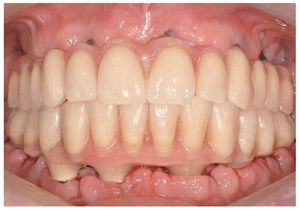

Pese a ello, es importante someter las estructuras a un control visual y mecánico, a fin de corregir eventuales discrepancias menores (figs. 99 a 102). A continuación se procede al montaje utilizando dientes protésicos prefabricados de composite (SR Phonares NHC, Ivoclar Vivadent, Ellwangen, Alemania), los cuales reproducen el tipo funcional correspondiente en virtud de sus propiedades morfológicas y estructurales y se integran armoniosamente en cuanto a su longitud dental (figs. 103 a 105). Durante la comprobación de las restauraciones protésicas, se evalúan clínica y radiológicamente ante todo la pasividad y la precisión del ajuste de la estructura. Acto seguido se lleva a cabo una comprobación de la oclusión y de la dimensión vertical, del estado de las prótesis y del tejido blando en la cresta alveolar, así como la verificación del espacio libre lingual, incluida la fonación, y el apoyo de los labios y las mejillas (figs. 106 y 107). También se debe comprobar la facilidad de higiene de la restauración de acuerdo con las habilidades manuales del paciente. A continuación se debe verificar la posición tridimensional de los dientes anteriores con los labios cerrados y durante la sonrisa, así como el aspecto global de la rehabilitación protésica.

Figs. 106 y 107. El control estético y gnatológico de las restauraciones protésicas definitivas.

Para la rehabilitación definitiva del paciente (figs. 116 a 124) deben comprobarse de nuevo todos los aspectos de la sesión anterior y debe procederse a la cementación de las prótesis. Son indispensables controles de seguimiento a corto plazo (al cabo de 1, 3 y 5 semanas) para el ajuste óptimo de la oclusión y la comprobación de la higiene oral con una prótesis que habitualmente ofrece aberturas de acceso periimplantares más estrechas que una prótesis provisional. Tres y seis meses después de la finalización del tratamiento se deben realizar controles clínicos, y una vez al año deberían llevarse a cabo sendos controles clínico y otro radiológico.

Figs. 116 y 117. Las restauraciones definitivas fijadas a los implantes. Cabe destacar la buena curación del tejido blando periimplantar.

Figs. 118 a 120. La situación intraoral final.